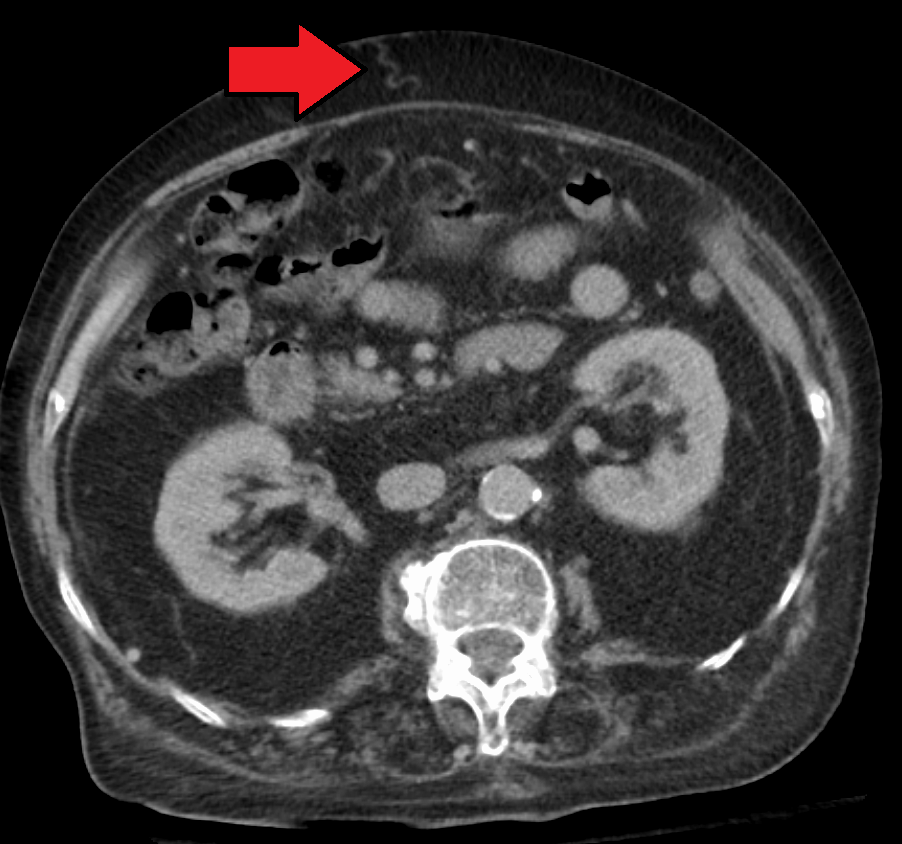

CT 스캔이나 MRI에서 간문맥이 팽창한 것이 보이면 문맥고혈압을 더 강하게 의심할 수 있다. 간문맥 직경의 기준치는 13mm가 널리 사용되지만, 정상인에서도 간문맥이 이보다 큰 경우가 자주 있다.[44][8]

직경이 13mm 또는 15mm 이상으로 팽창된 간문맥은 문맥고혈압의 소견으로, 민감도가 12.5~40% 정도이다.[51] 도플러 초음파검사에서는 혈류 속도가 16cm/s 아래로 느리고 간문맥이 팽창되어 있다면 문맥고혈압을 진단할 수 있다.[52] 초음파상에서 문맥고혈압의 또 다른 소견으로는 혈류의 평균 속도가 12cm/s보다 느리거나, 곁순환을 이루는 정맥(열린 상태의 배꼽옆정맥, 비장과 콩팥의 곁순환, 팽창된 왼위정맥과 짧은위정맥)이 존재하는 경우, 지라비대, 간경변증의 소견(간 표면의 결절 형성) 등이 있다.[50]